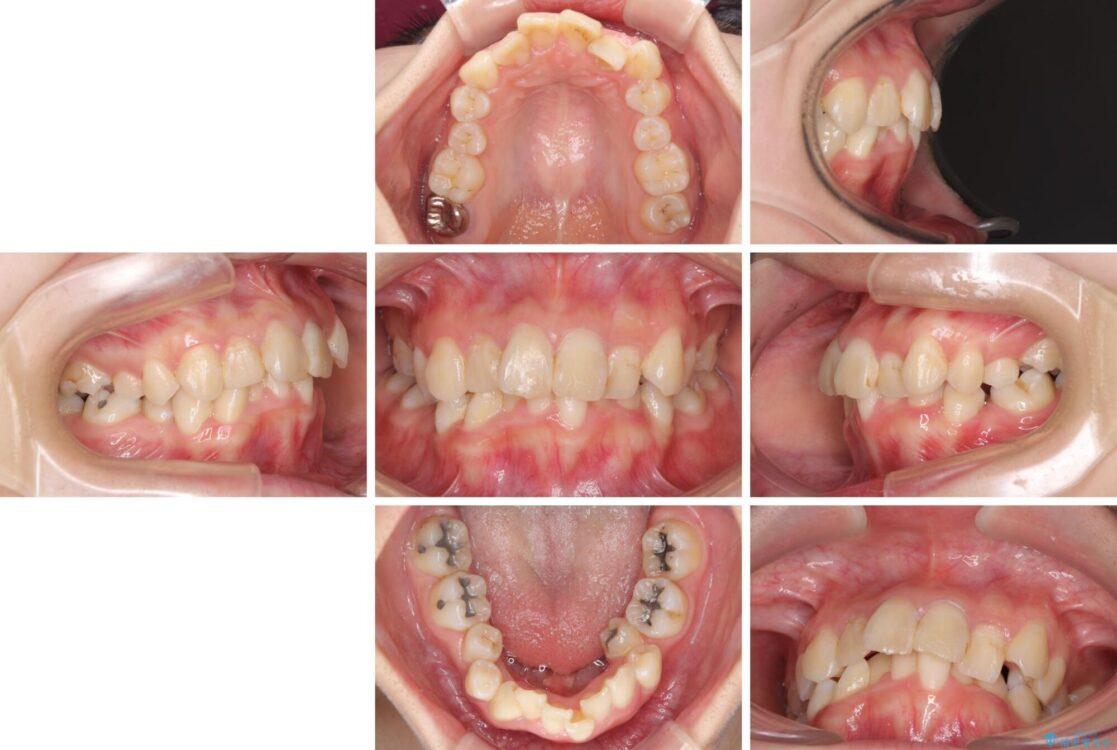

治療後

• デコボコと深い咬み合わせ ワイヤー装置での抜歯矯正 治療後画像